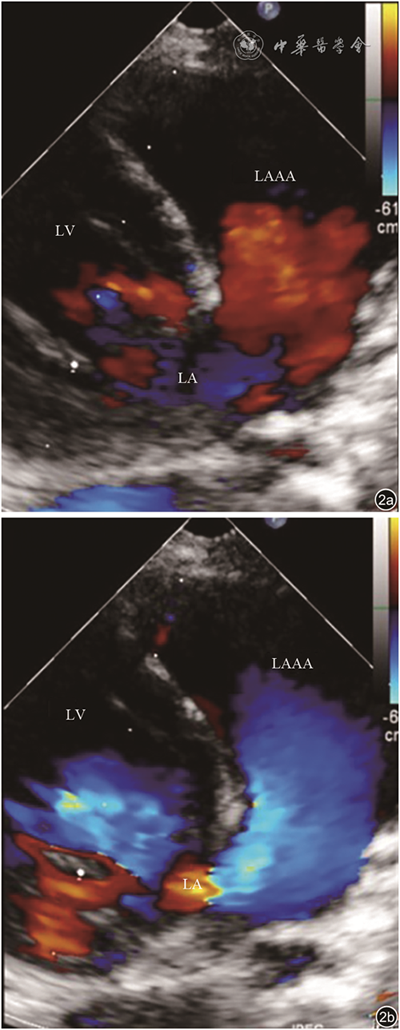

9例患者均经超声心动图检查诊断为LAAA,表现为:(1)四腔心、心底短轴、剑突下等切面二维超声图像可见左心室游离壁外囊状无回声结构,为LAAA;(2)LAAA与左心房交通(图1);(3)彩色多普勒可见LAAA与左心房间血流信号往返(图2);(4)巨大LAAA可压迫左心室或其他毗邻结构(图3);(5)同时可显示合并的其他占位性病变(图4)。

图1 左心耳瘤不同切面二维超声图像,可见左心室壁外侧囊状无回声区,与左心房交通,合并存在室间隔缺损。图a为心尖四腔心切面;图b为心底短轴切面;图c为剑突下四腔心切面